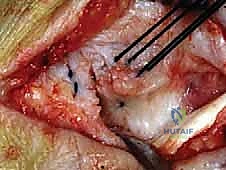

الخطوة الرابعة: تقييم وإصلاح رباط الدالية (Repair vs. Reconstruction)

بمجرد الوصول إلى رباط الدالية، يتم تقييم درجة التلف:

* الإصلاح المباشر (Direct Repair): إذا كانت أنسجة الرباط الممزقة ذات جودة جيدة (عادة في الإصابات الحديثة)، يقوم الدكتور هطيف بخياطتها مباشرة. يستخدم خطاطيف تثبيت عظمية (Suture Anchors) صغيرة جداً ومصنوعة من مواد متوافقة حيوياً (تذوب مع الوقت أو من التيتانيوم) لغرس الخيوط القوية في عظمة الكعب الإنسي، ثم يتم سحب الرباط الممزق وتثبيته بقوة في مكانه التشريحي الأصلي.

- إعادة البناء (Reconstruction): في الحالات المزمنة حيث يكون الرباط الأصلي قد تليف، تآكل، أو أصبح غير كافٍ للاستخدام، يلجأ الدكتور هطيف إلى تقنية "إعادة البناء". تتضمن هذه التقنية المتقدمة استخدام رقعة وترية (Graft)، إما من جسم المريض نفسه (Autograft - مثل أوتار الركبة أو وتر من القدم) أو رقعة صناعية متطورة. يتم حفر أنفاق ع